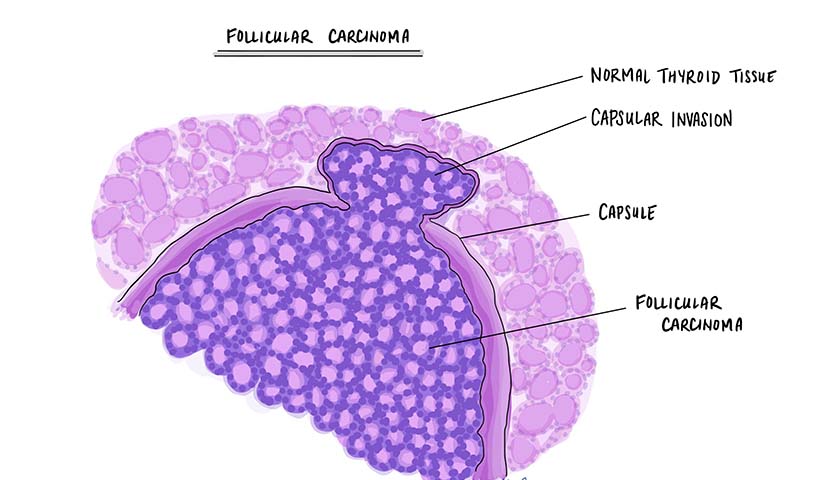

ما هو سرطان الغدة الدرقية الجريبي؟

الغدة الدرقية هي غدة توجد في الرقبة، وهي جزء من نظام الغدد الصماء لدى الإنسان، وسرطان الغدة الدرقية الجريبي هو أحد أنواع سرطان الغدة الدرقية الذي تنمو فيه الخلايا وتتطور بطريقة سريعة وغير طبيعية، بالتالي تتأثر كمية الهرمونات المفرزة من الغدة الدرقية والتي تعمل على تنظيم عملية التمثيل الغذائي، والتي تحافظ على مستويات الكالسيوم في الدم.

سرطان الغدة الدرقية الجريبي ليس شائعًا، فهو يمثل فقط 10% من أنواع سرطان الغدة الدرقية، مع ذلك وفي بعض الحالات، يصعب تشخيص هذا المرض، وفي هذه الحالة، يحتاج الأطباء إلى إجراء عملية جراحية لاستئصال الفص وتأكيد التشخيص قبل وضع خطة العلاج.